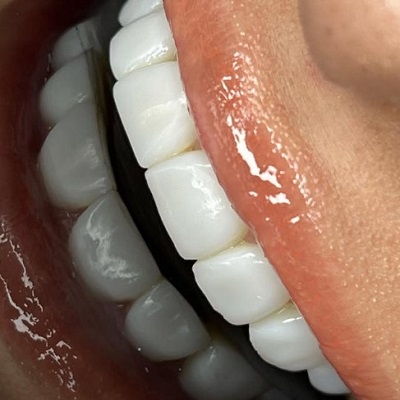

دکتر مهدی عرفانیان تقوایی

دکتر مهدی عرفانیان تقوایی، متخصص جراحی های زیبایی و ترمیمی دندان و از برجستهترین جراحان در زمینه جراحیهای پیچیده فک و زیبایی دندان مانند پروتز فک هستند. با دانش و تجربه فراوان، ایشان درمانهایی دقیق و نتایجی طبیعی و ماندگار برای بیماران ارائه میدهند.

- کاشت ایمپلنت دیجیتال

- نصب و طراحی پروتز فک

- درمان کیست و تومورهای فک

- اصلاح ناهنجاری های مادرزادی فک و صورت

مشهد، چهارراه دکترا، روبه روی پارکینگ طبقاتی بیمارستان امام رضا)، نبش ابن سینا 7، ساختمان پزشکان سینا ، طبقه 4، واحد 401